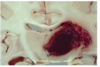

the condition seen in the image is caused by rupture of ____

the condition seen in the image is caused by rupture of bridging veins (low press so gradual onset)

explain how the condition seen in the image is also seen in babies

shaken baby syndrome → rupture d/t thin walls of veins

the condition seen in the image causes an increase in ____ with which 4 signs?

the condition seen in the image causes an increase in ICP with:

on CT in the condition seen in the image, there is ___ with a ____ because ____

crescent hematoma with a midline shift because it is closer to the brain

a complication of the condition seen in the image is ____

a complication of the condition seen in the image is uncal herniation

the condition seen in the image is caused by rupture of ____ where the blood collects between ____ & ____

the condition seen in the image is caused by rupture of middle meningeal artery → blood collects in epidural space between dura & calvarium

the condition seen in the image is caused by a lateral blow to ___

the condition seen in the image is caused by a lateral blow to temporal side of head

describe the presentation of the condition seen in the image

lose consciousness → lucid interval → death

increase in ICP → headaches, projectile vomiting, blurry vision, papilledema

on CT of the condition seen in the image, there is a ____ shaped hematoma

on CT of the condition seen in the image, there is a biconvex lens shaped hematoma

a complication of the condition seen in the image is \_\_\_

a complication of the condition seen in the image is **uncal herniation**